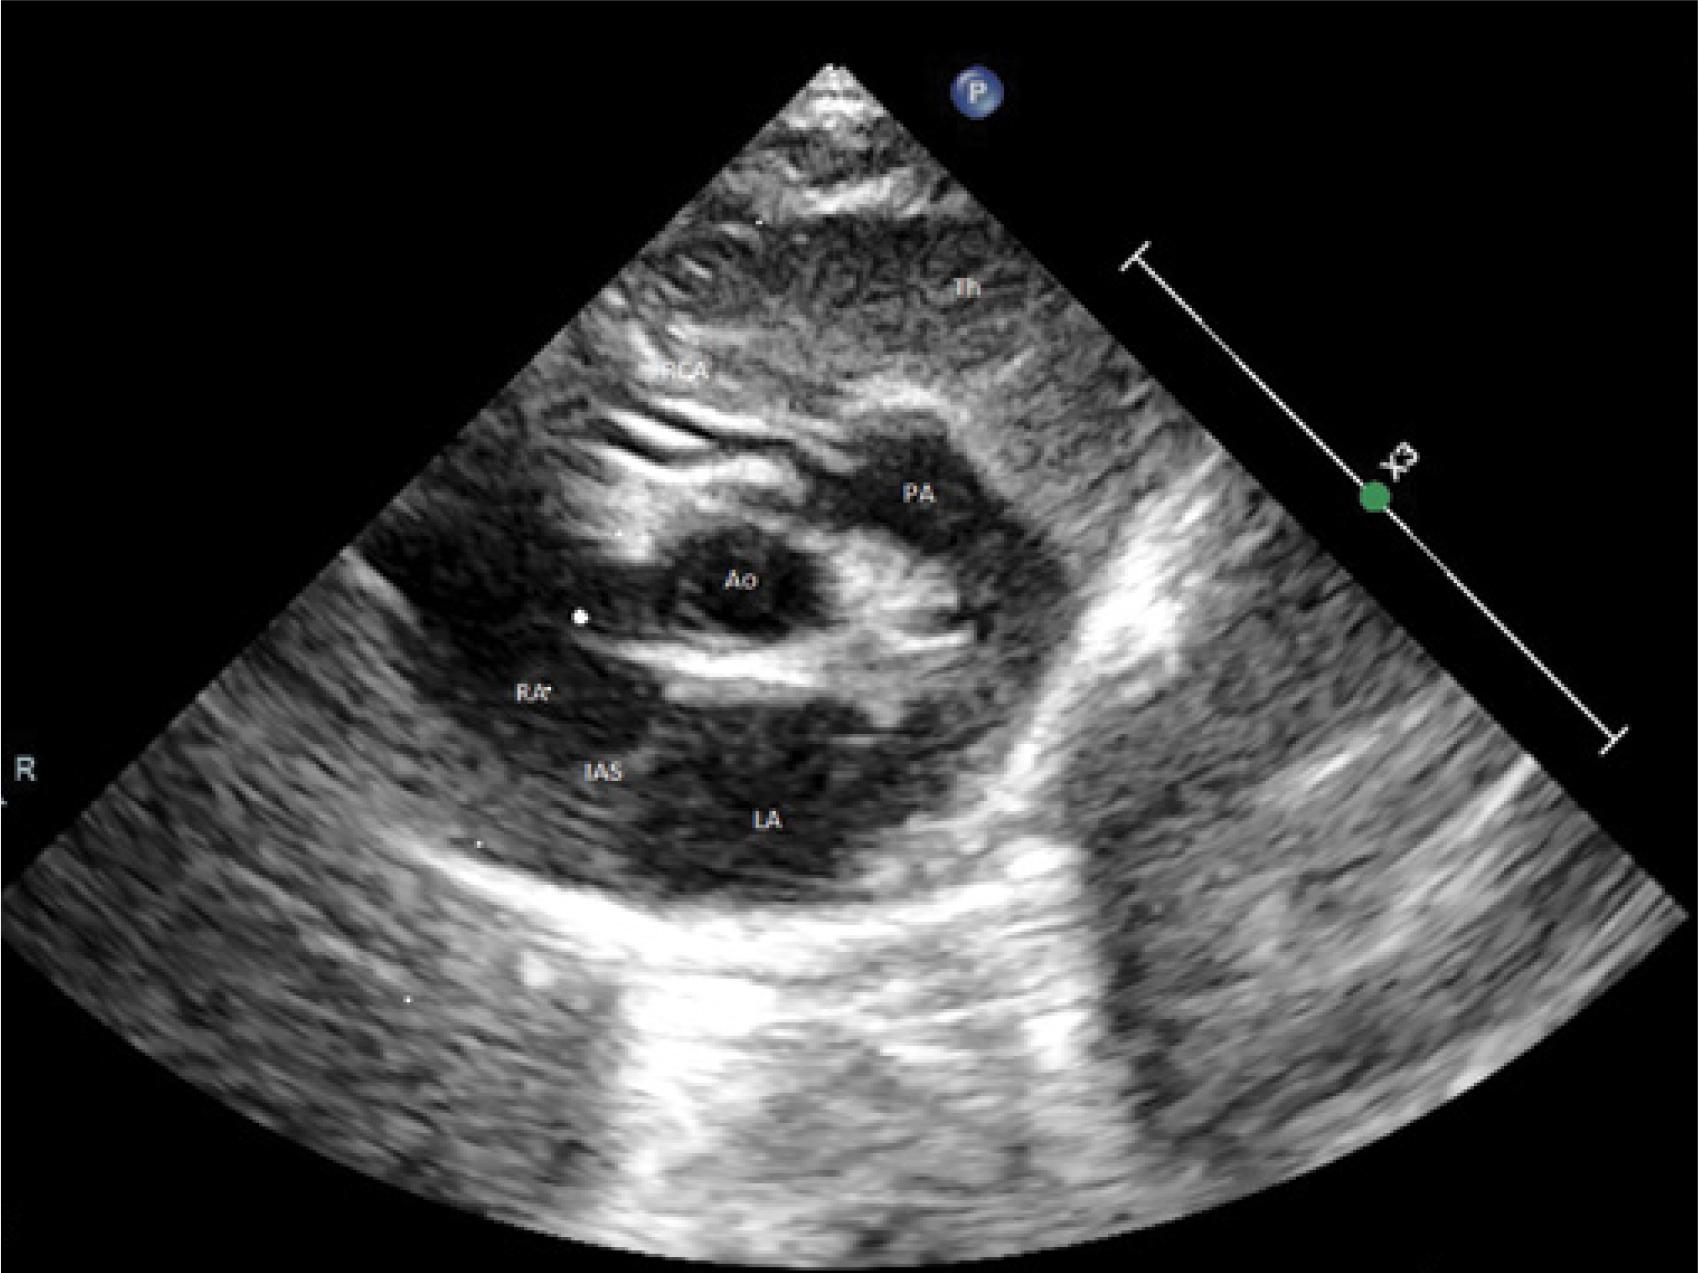

Fig. 2

Preoperative ECHO. Modified cross-sectional parasternal vascular projection. See the inflow from the right coronary artery to the pulmonary artery. Ao – cross-section of the ascending aorta, PA – pulmonary artery trunk, RCA – right coronary artery, RVOT – right ventricular outflow tract, RA – right atrium, Sh – RCA-PA shunt.